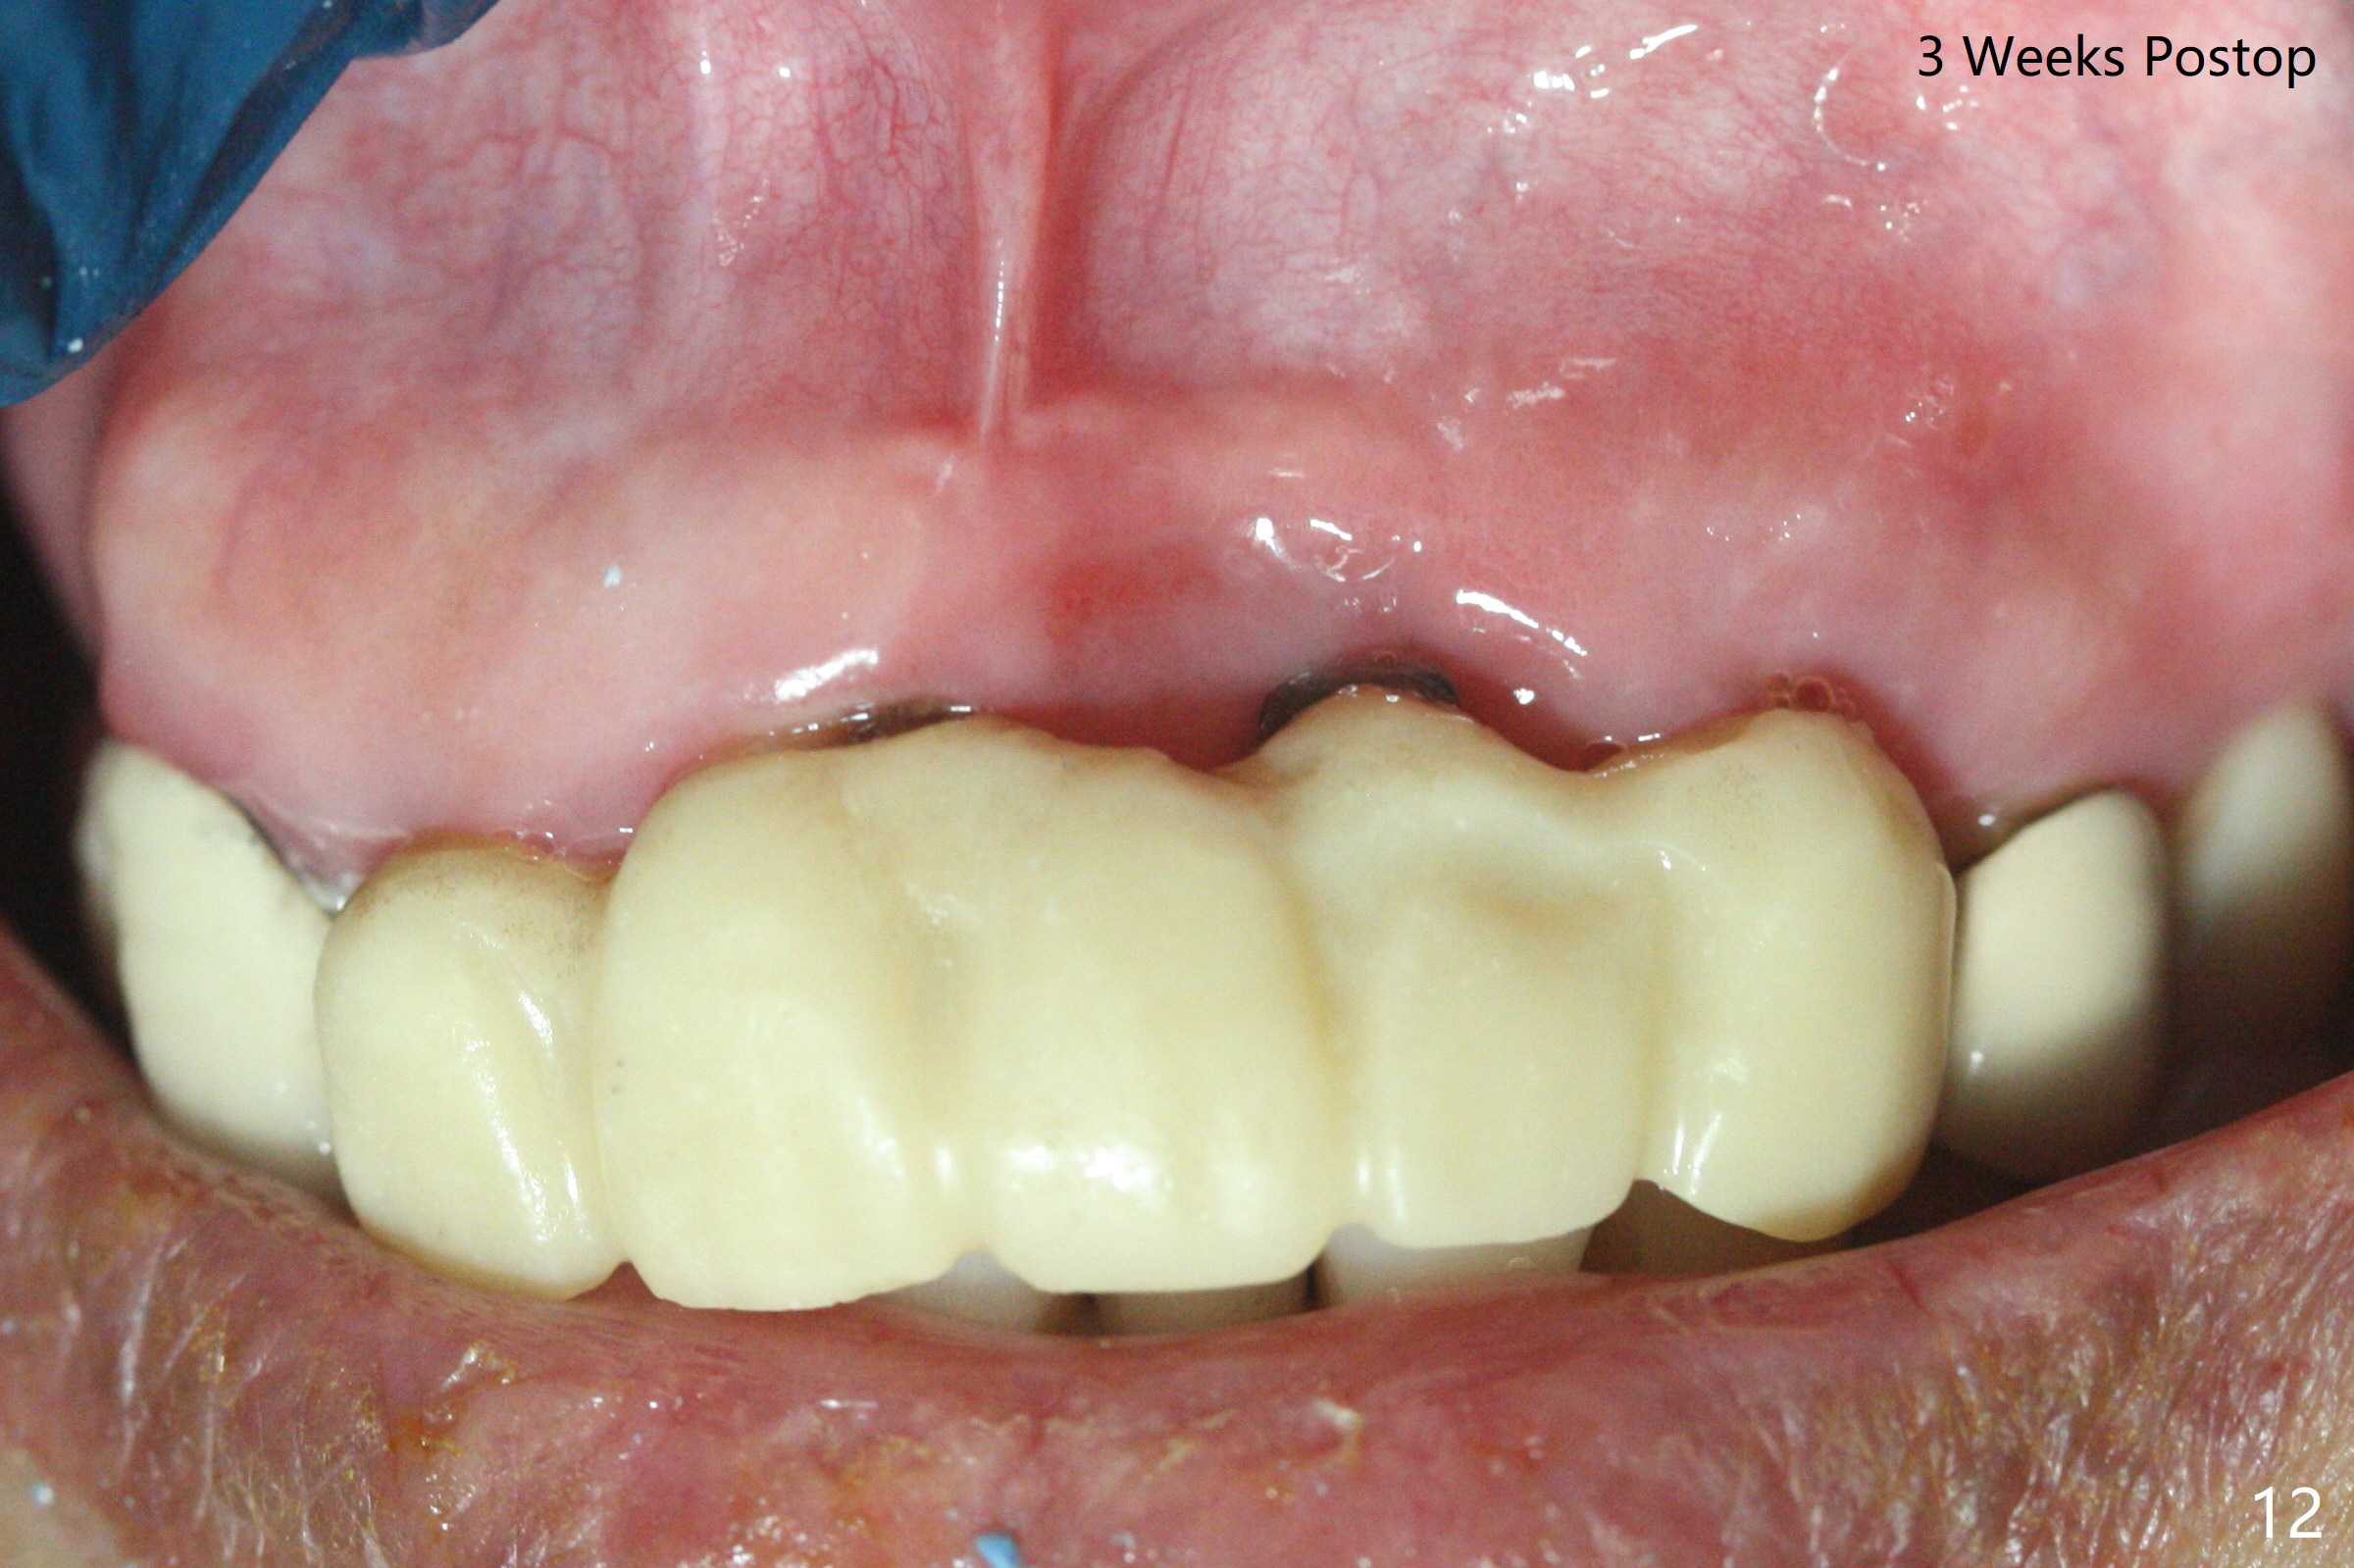

上前牙桥撤除显示右上1,2牙齿以及左上2叶片状植体好像可以保留,而左上3牙齿不能(图一,二(<:托牙边缘压迹)),拔除左上3牙齿后, 暂时把牙桥回位(图三:FPD(已经去除左上3号牙牙冠))作为3号牙种植位置参考(图四至六(G:骨粉))。其实植入前,当最后一个钻头还在原位,将PRF膜和粘性骨放置颊侧根尖(但愿骨粉能放深点),因为那里骨质很薄,好像缺损。由于植体扭力很低(大约5Ncm),放置骨粉覆盖植体(图七),为了不用缝线,涂牙周胶水(图八),放置胶原膜(图九),再涂胶水(图十)固定,最后利用右上1,2号牙(去龋,build-up后)和左上2植体制作临时牙桥,并且覆盖左上3牙槽窝。术后即刻CT显示植体颊侧(B)骨粉(图十一:*)。<:植体根尖仍有间隙,植体应该再长2毫米,初步稳定性会好些。左上3植牙愈合后,将与左上2植体制作左上1-3悬臂桥,右上1,2号牙将做根管治疗,桩,牙冠。临时牙桥术后十一天松动,右上一,二牙牙髓活性测定正常,深洗后,再次build up,不小心把左上3胶原膜吹掉,下面骨粉还稳定。术后三周病人回来做右上六种植,前牙临时修复体(图十二)需要修改(图十三)。拍摄三个方向照片显示前牙牙龈乳头(颊侧和咬合面)。

The mesiobuccal margin at #8 is redefined 4 weeks postop (Fig.14) so that the cervical end of the temporary crown is able to move mesially (Fig.13). The most coronal portion of the bone graft at #11 begins to be detached (*). The mesial portion of the abutment at #10 will be removed (curved white line) in the following week. After removing the most coronal portion of detaching bone graft at #11, acrylic is added to form a concave pontic (Fig.15 ^). With removal of the mesial portion of the abutment at #10, the retainer is moved distal (>). Pontics form at UL1 and 3 two months postop (Fig.16 *), while there is buccal atrophy at UL1,2 (Fig.17). 术后3个月植牙区牙龈形态良好(图十八),即将暴露,放置愈合基台。图十九是在右上1根管治疗时(基台放置后五天)拍摄。左上3术后3个月3个星期,1,2唇侧塌陷(图二十)。叶状植体处牙槽嵴往根尖萎缩(图二十一:^)。尽管做了松弛切口,放入事先预备的粘性骨粉后,几乎没有空间放置结缔组织移植物,恰好还没有取。放置PRF膜后,使用4-0 Monoglyc缝线缝合。牙龈似乎冠方移位(图二十二:箭头)。植骨后,唇侧仿佛饱满多了(图二十三:*)。骨粉放置于左上1,2唇侧和牙槽嵴(图二十四:*,与之前(图十九)对比)。后者有助于牙龈冠方移位,而前者有助于增加唇侧饱满度。植骨术后两周唇侧仍饱满(图二十五,六)。植骨后四个月牙冠粘固,两个月后,病人抱怨10号牙左右食物坎塞(图二十七),9/10牙冠撤除,10基台边缘加深,重做临时牙冠,同时增加9凹陷(pontic)。一个月后,9/10临时牙冠修整两次,11永久性牙冠撤除,也制备临时牙冠,外形明显改善(图二十八)。